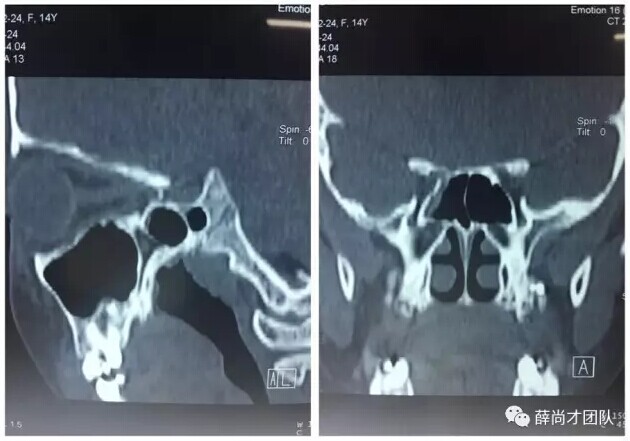

甘肃省二院眼科开展经眼眶视神经减压术使许多外伤失明的患者重见光明------2017-04-28 发布时间:2017-04-28 来源: 作者: